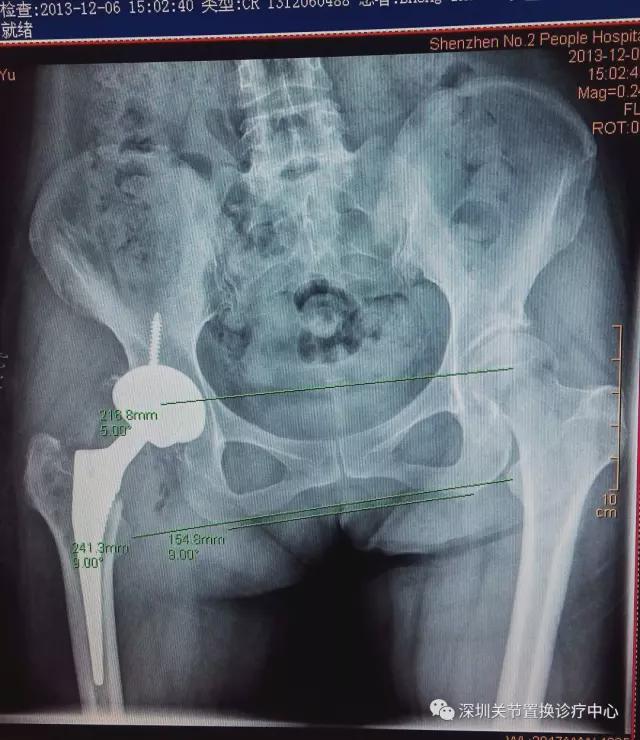

术前X线片

我的天,松动!感染!脱位!人工髋臼都翻转啦!